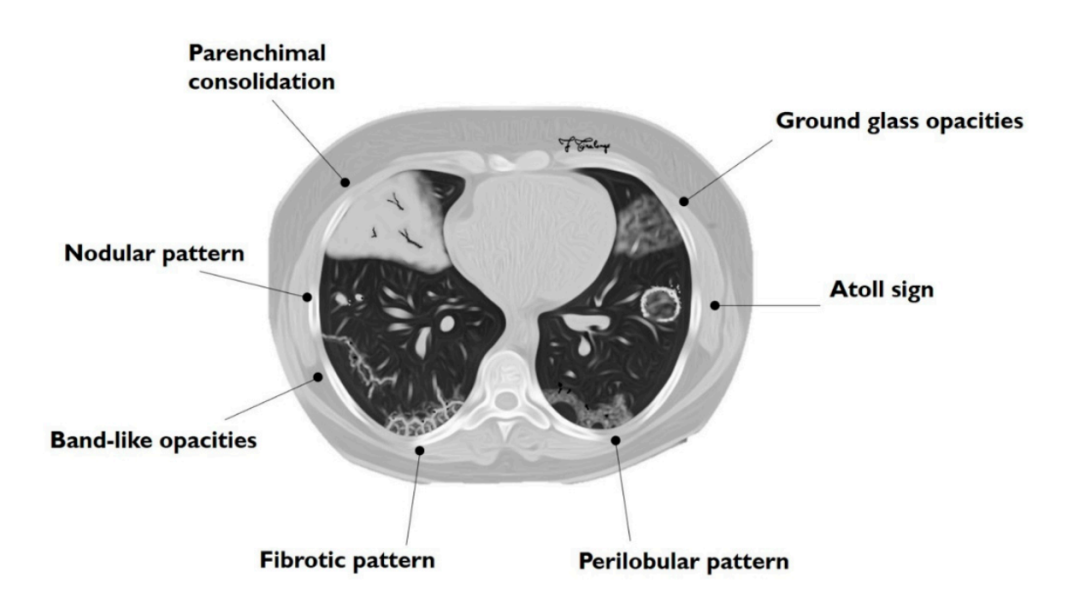

2. 影像学表现

①肺实变磨玻璃密度影;②小叶周围阴影;③环礁征;④结节或肿块;⑤小叶间隔增厚;⑥束状或条带阴影;⑦进行性纤维化。

图片

隐源性机化性肺炎主要的影像学表现

图片来源:Diagnostics (Basel), 2020, 10(5):262.

3. 影像学特点

(1)典型影像:斑片状肺泡浸润影(典型COP)。

(2)不常见影像:孤立性阴影(局灶性COP);浸润性阴影(浸润性COP)。

(3)少见影像:反晕轮征;进行性肺纤维化并网格及实变;多发性结节;支气管中央型实变;不规则线或带状影;小叶周围型阴影。